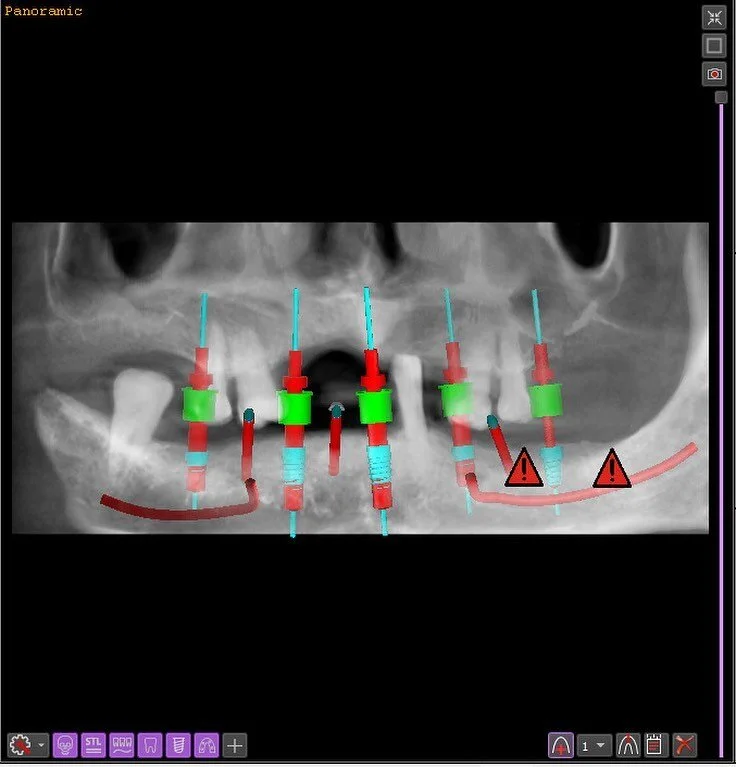

Several dentists who attended How To Plan & Print Surgical Guides For Guided Dental Implant Surgery gave it a stellar review!

"The course was very good and everyone was very nice. I would recommend this course to anyone that wants to learn how to use Exoplan and see how to make a surgical guide."